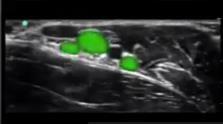

Axillary Veins Image

Highlighted Area: Axillary Veins